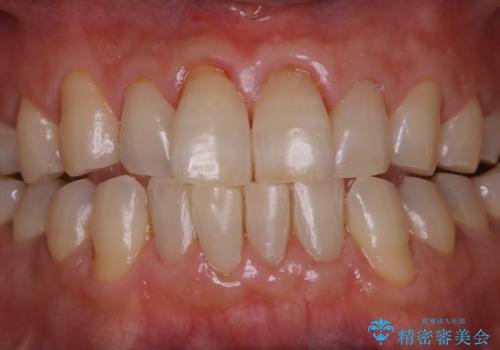

インビザラインでのマウスピース矯正中にPMTCで着色をきれいに

- インビザラインでの矯正治療中の方です。コーヒーをよく飲むため、着色が気になるとのことでした。PMTC60分コースを行いました。

毎日丁寧に歯磨きをしていても、日常生活での飲食物などにより着色してしまうことはあります。

PMTC(保険外治療)は、毎日の歯磨きで落としきれない汚れや、コーヒ、紅茶・タバコのヤニなどの着色も除去します。目には見えない歯と歯の間・歯肉の境目・インビザライン中はアタッチメント周囲などに残っているプラーク(歯垢)もしっかり取り除きます。PMTCでは専門的な機械や材料を使用して、徹底的に汚れを除去するため、虫歯・歯周病・口臭予防などにつながります。

また、仕上げのトリートメントでは歯の表面の凸凹にミネラルを補給して、ツルツルの表面に仕上げます。定期的にPMTCを行うことにより、歯質の強化になり着色がつきにくい状態になります。